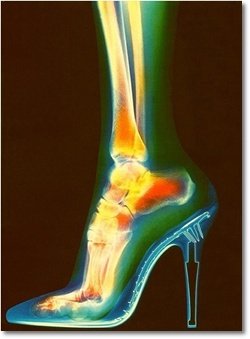

여성분들 같은 경우에는 일하실 때 하이힐을 신도록 되어 있는 경우가

상당히 많은데요 하이힐을 신을 경우, 여자분들 이 앞으로 쏠리게 되잖아요?

이걸 균형을 맞추기 위해 우리의 근육이 끊임없이 수축 이완을 하게 되는데, 이렇게 될 경우

종아리 근육에 수명을 단축시키고 무릎이나 등을 아프게 한답니다. 또 균형을 못맞추고 넘어질 확율도 증가.